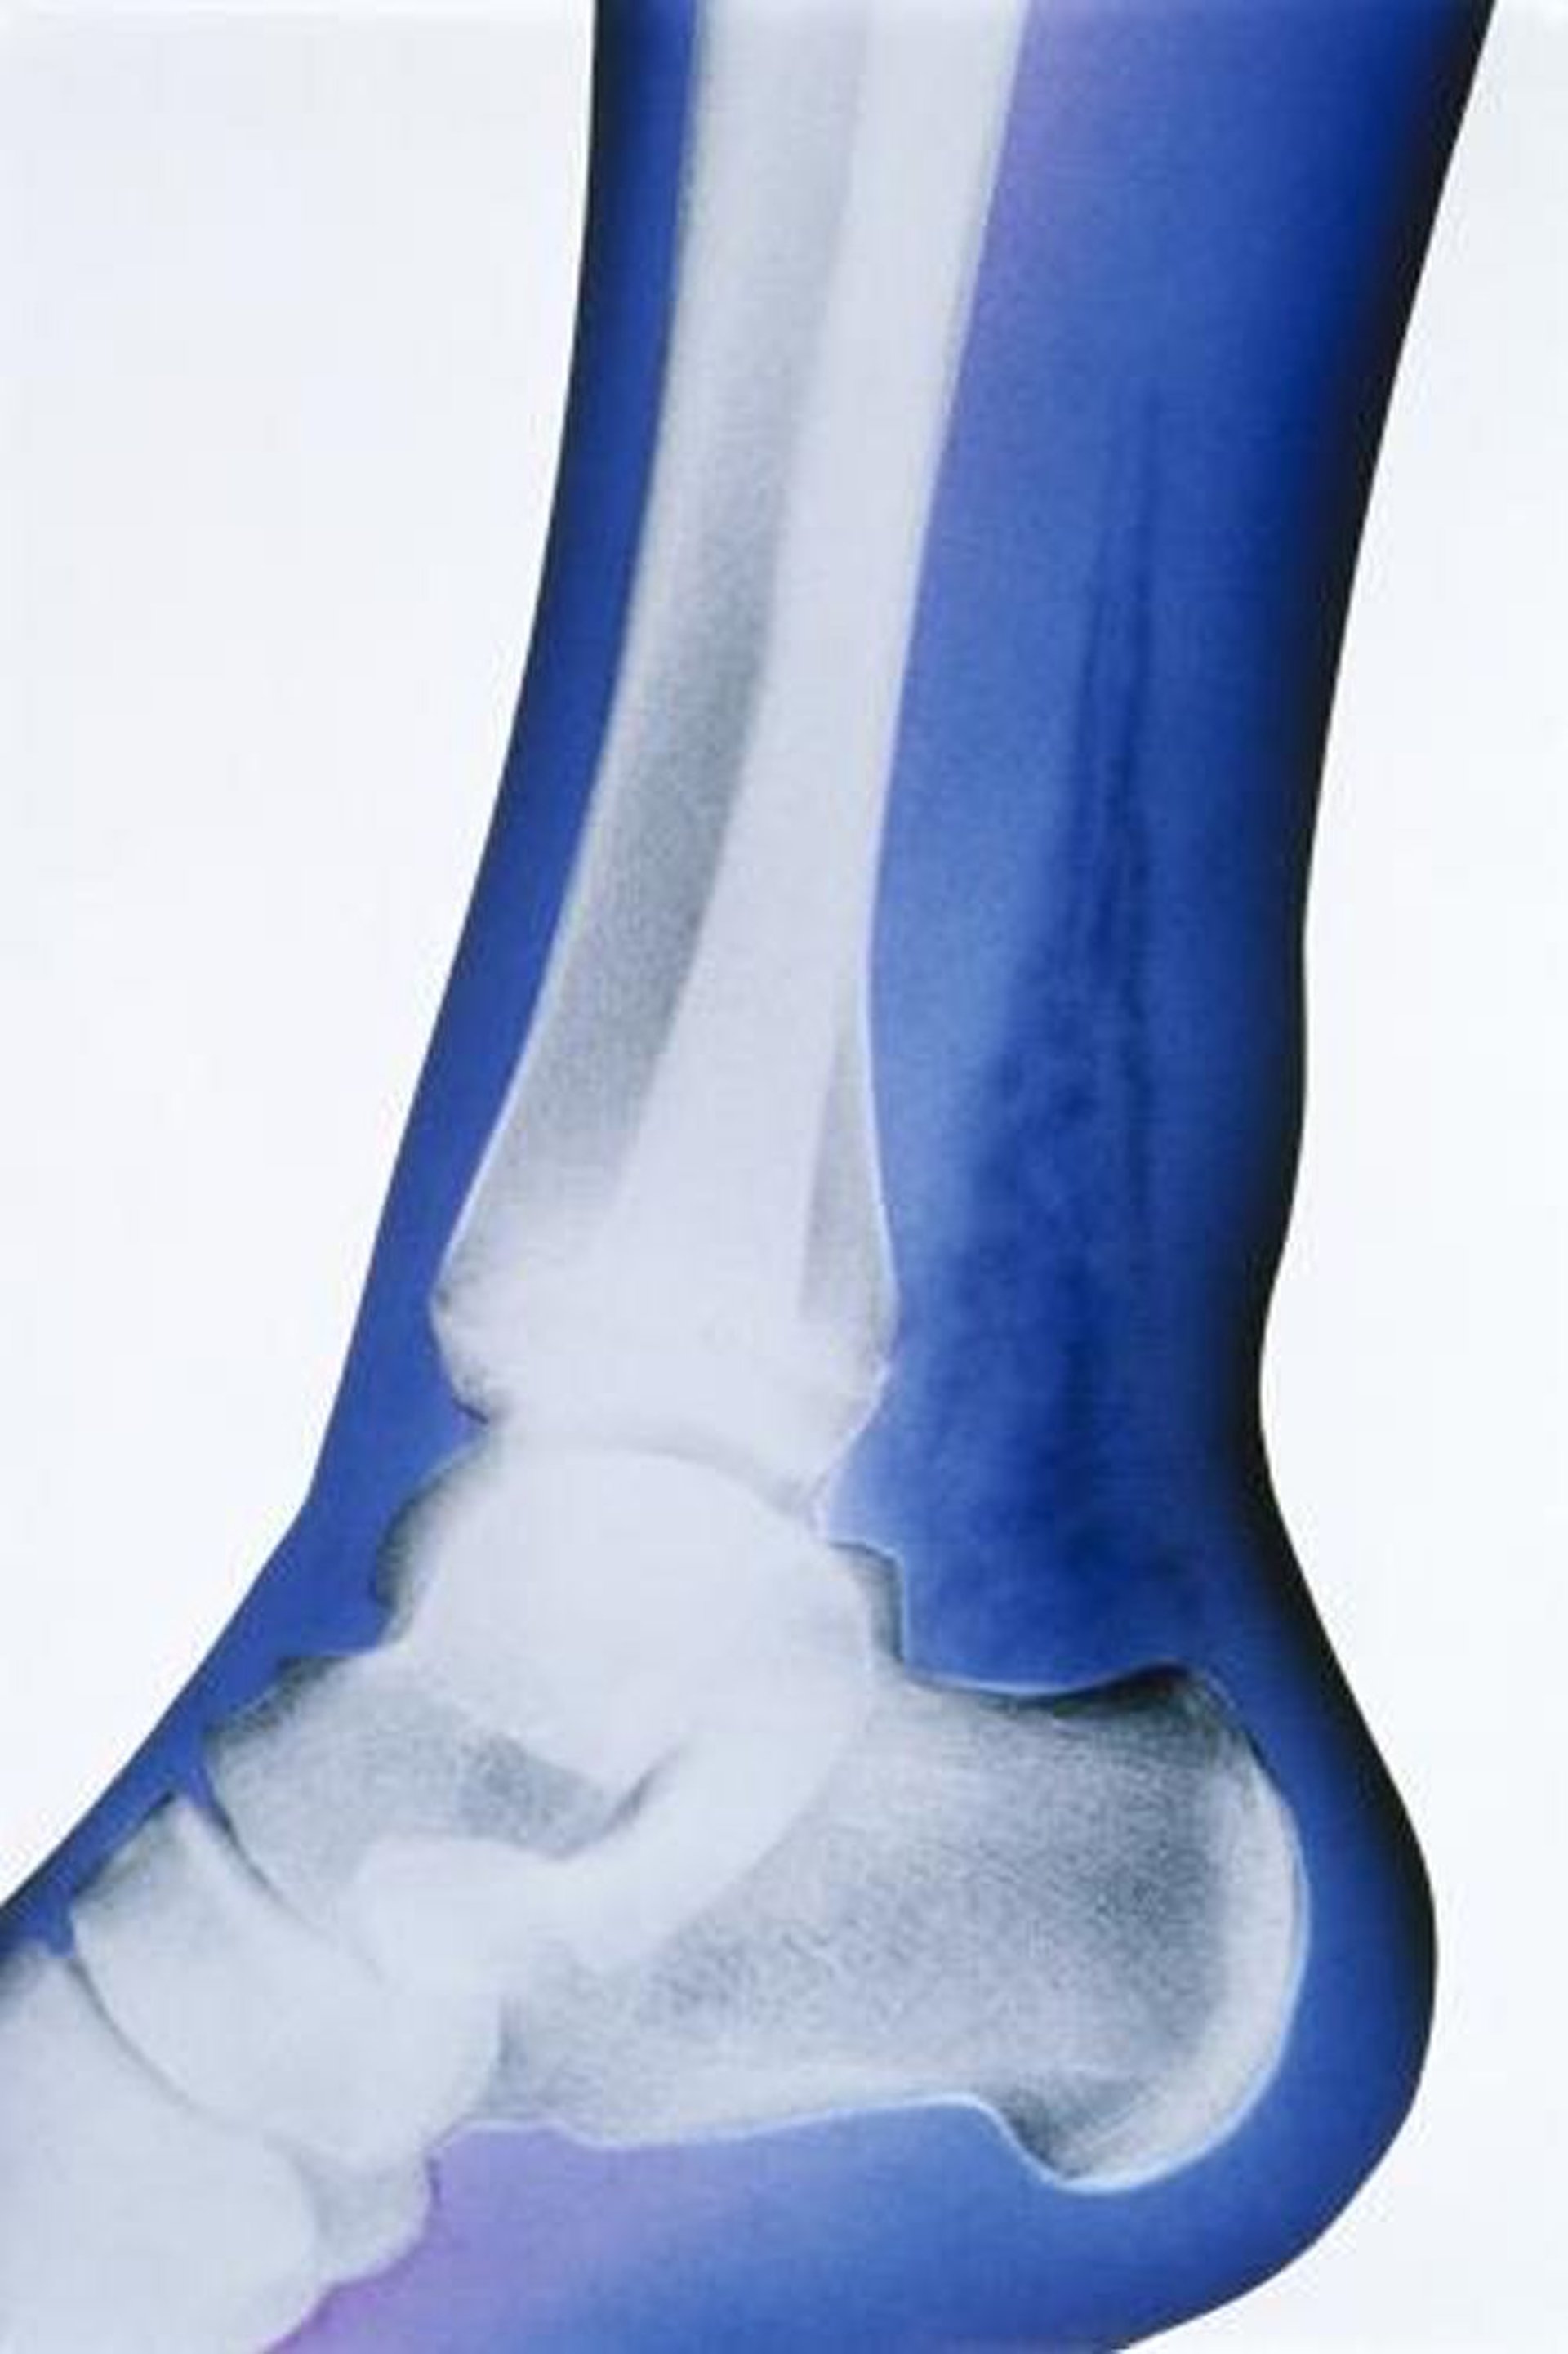

Infección subcutánea necrosante (radiografía)

En esta radiografía coloreada artificialmente, el hallazgo más sobresaliente es la presencia de gas en los tejidos blandos, indicado por las densidades altamente radiolúcidas encima del calcáneo y detrás de la tibia y el peroné.